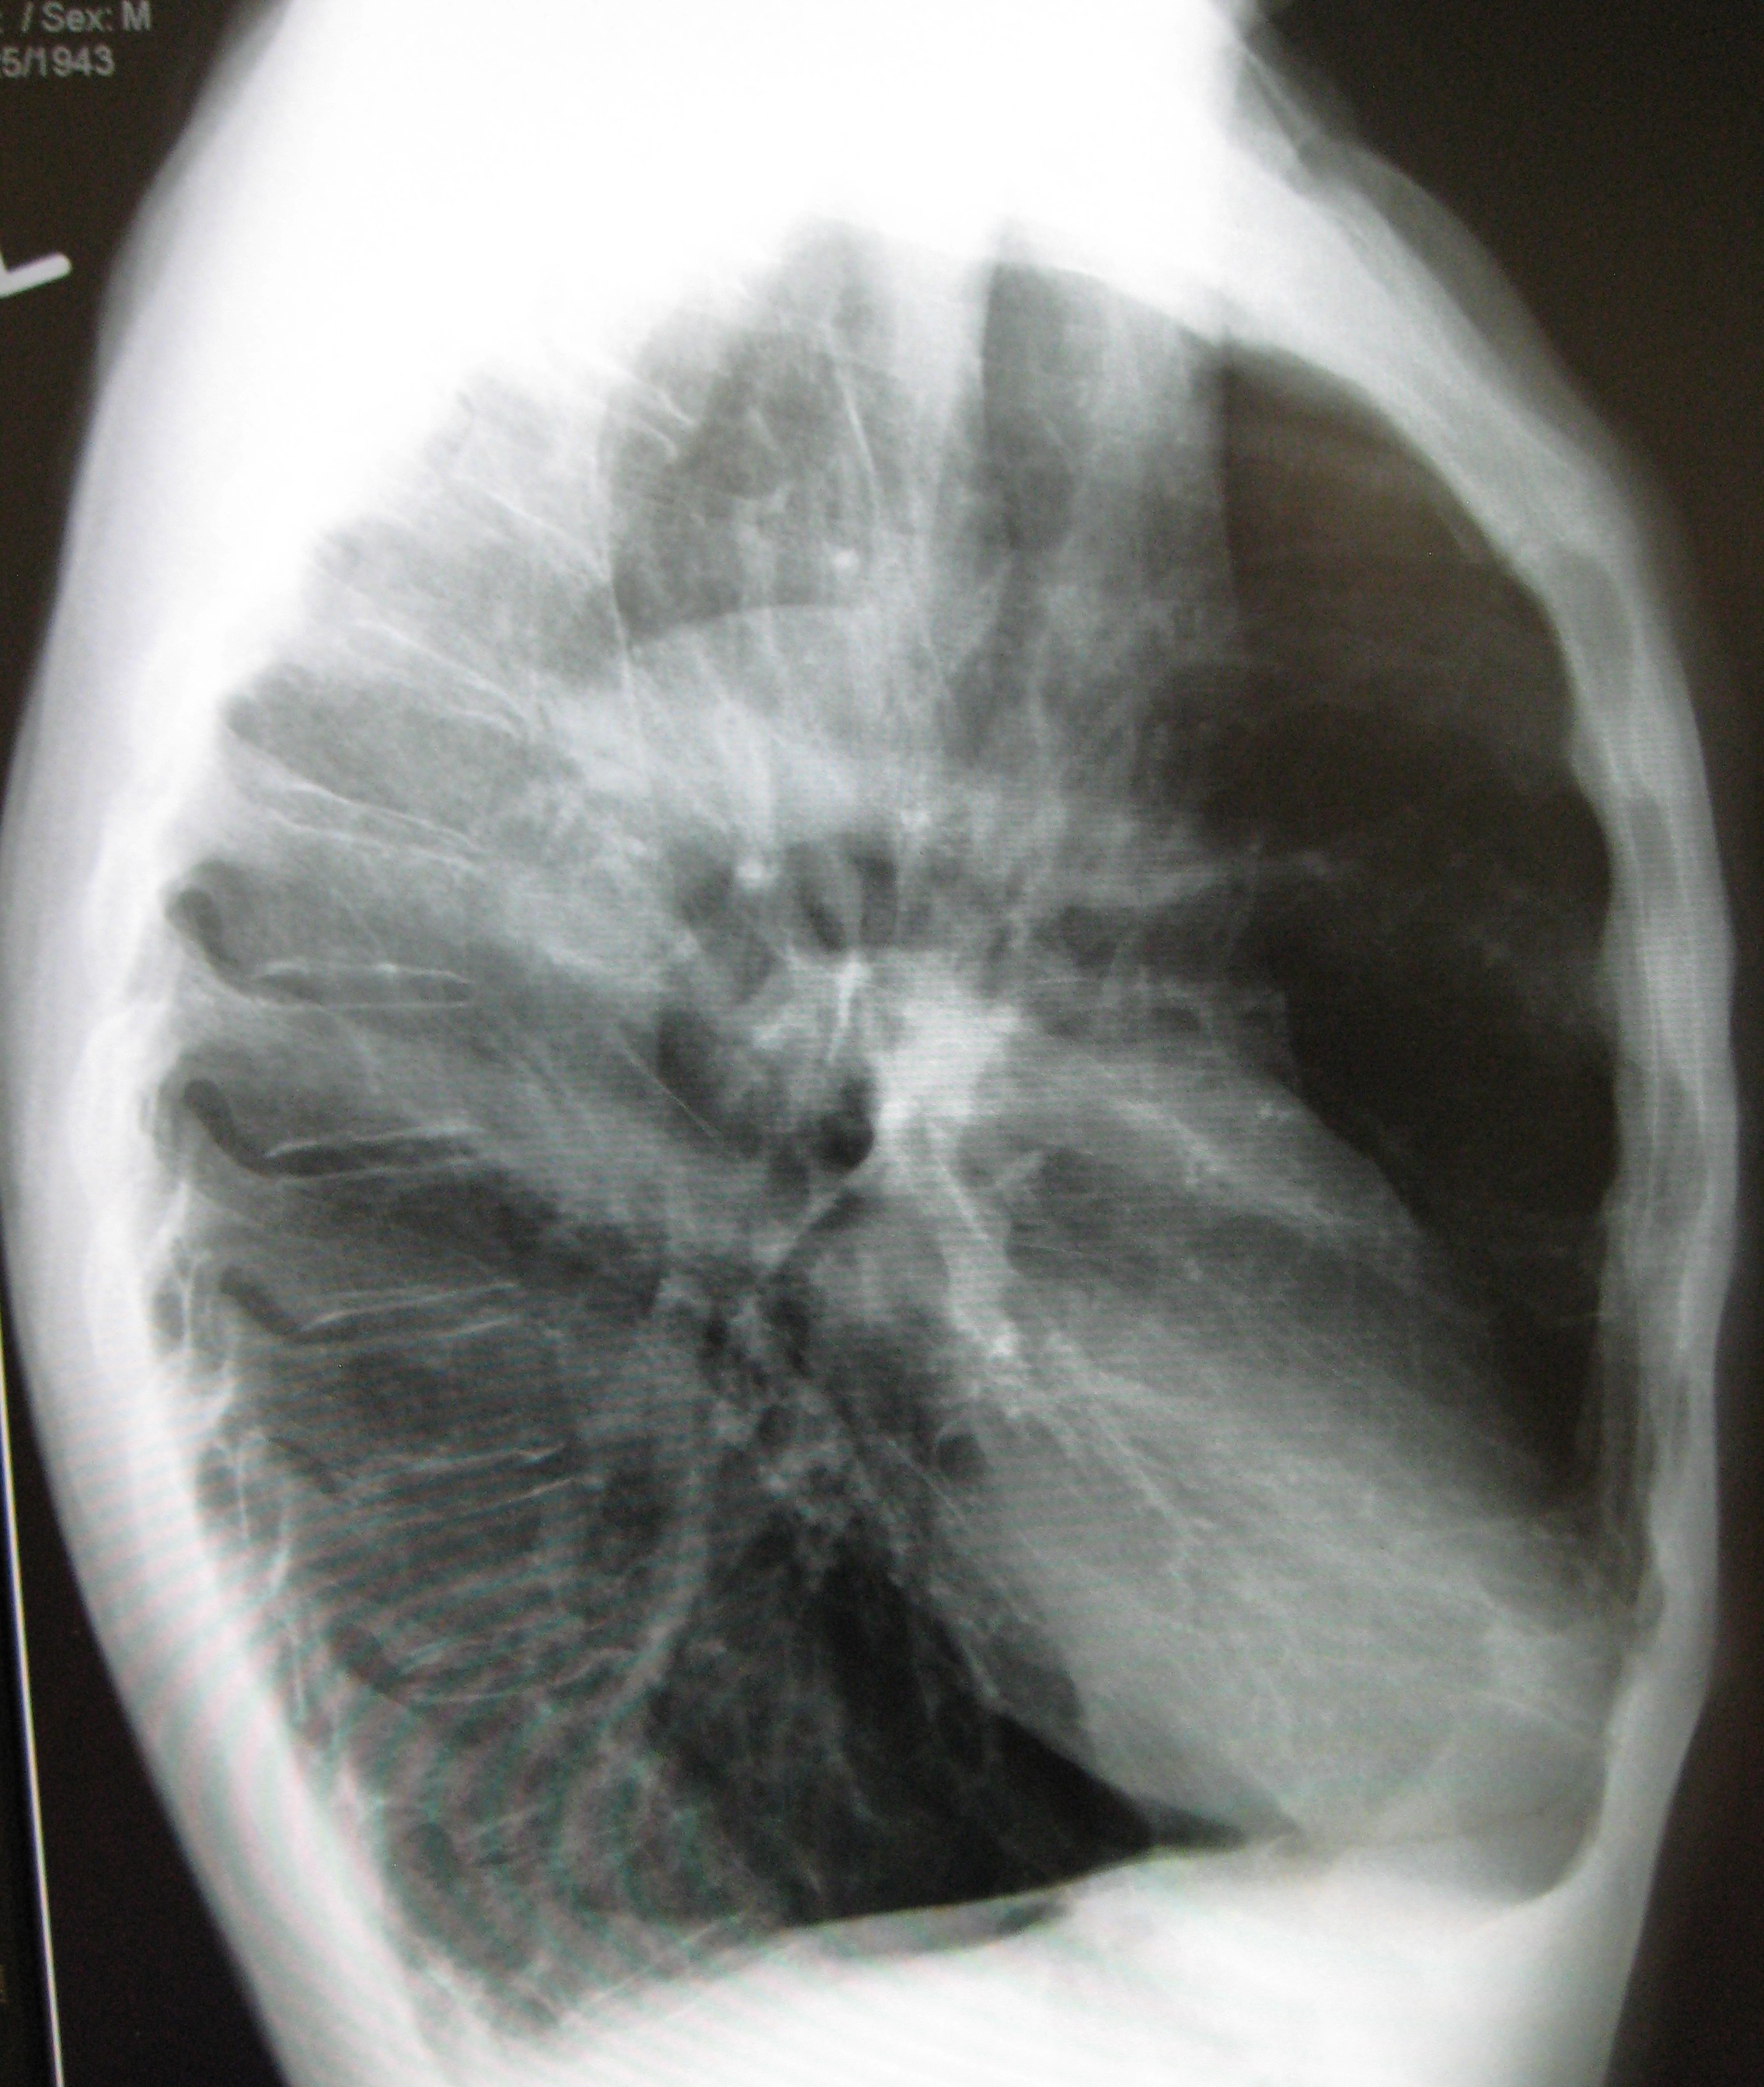

Howstuffworks.com contributors chronic obstructive pulmonary disease (co. Emphysema - wikidoc

Emphysema - wikidoc from wikidoc.org